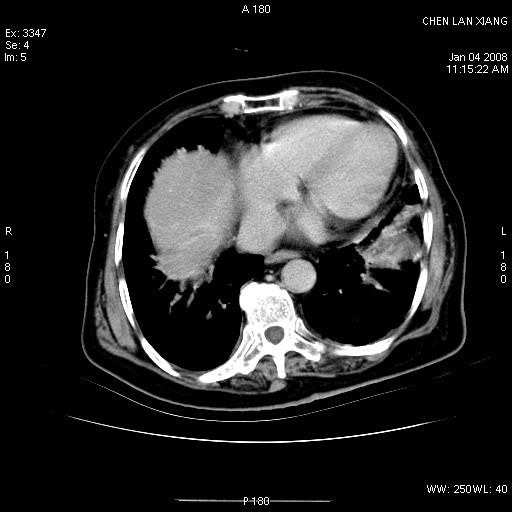

女,76岁,腹痛3-4天,b超示:肝内实性肿物,胆囊强回声,胆总管扩张.

标题: 肝右叶病灶

胆囊癌侵犯肝右叶?

1)胆囊癌伴肝脏转移。2)胆总管下端结石、肝内胆管结石伴肝内外胆管扩张。